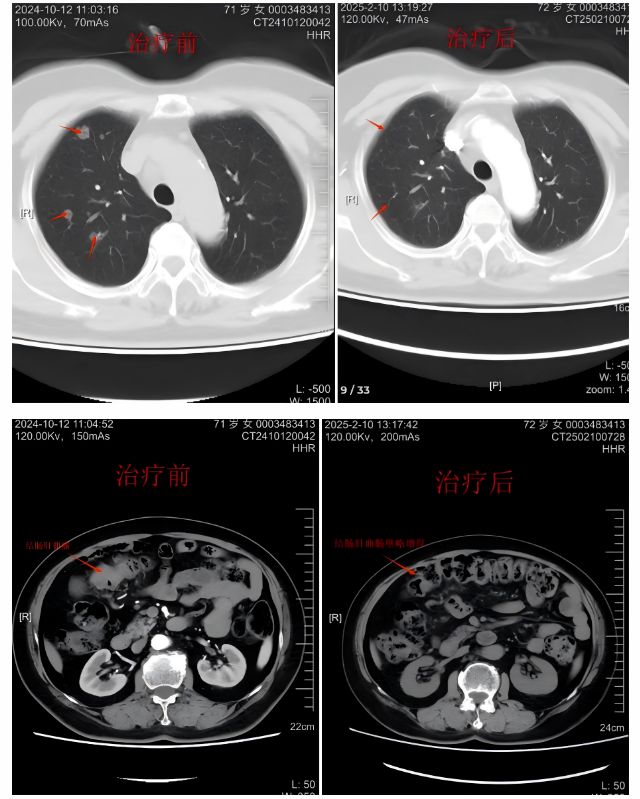

半年前,李大娘因腹痛、便秘就诊,肠镜确诊结肠肝曲恶性肿瘤,PET-CT更提示双肺多发转移。面对肠癌晚期转移的残酷诊断,哈医大四院普外一科(胃结直肠外科)迅速启动MDT多学科会诊。结直肠外科陈洪生教授团队及肿瘤内科团队结合基因检测结果,制定出"以XELOX方案为基础的化疗+贝伐珠单抗靶向药物"的联合治疗方案。治疗过程中,团队通过循环肿瘤DNA动态监测,实时调整药物组合,两个月后第一次复查显示肺部多发转移病灶明显缩小。

经过四个疗程的靶向+化疗治疗,在第2次评估时,影像报告让所有人振奋——双肺转移灶完全消失,原发肠癌病灶明显缩小,肿瘤指标趋近于平衡。抓住治疗窗口期,陈洪生教授团队为患者实施腹腔镜右半结肠癌根治术,膜解剖理念下D3清扫,精准切除病灶及周围淋巴结,术后病理分期pT2N1M0,肿瘤已缩小到直径不足1cm,周围淋巴结转移1/32。围手术期贯彻ERAS理念,个体化管理,早期离床活动、恢复胃肠道功能,患者术后1周顺利康复出院,择期来院继续进行术后的辅助抗肿瘤治疗,我们有充足的信心,患者会有一个良好的预后。